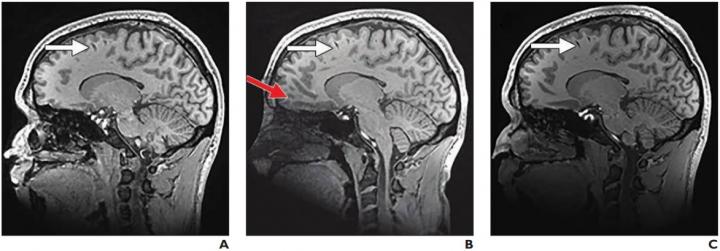

Leesburg, VA, December 3, 2020--According to an article in ARRS' American Journal of Roentgenology ( AJR ), a prototype 16-channel head Adaptive Image Receive (AIR) radiofrequency coil from GE Healthcare outperformed a conventional 8-channel head coil for in vivo whole-brain imaging, though it did not perform as well as a conventional 32-channel head coil.

Imaging a phantom and 15 healthy adult participants, Cogswell and colleagues used clinically available MRI sequences to compare their 16-channel head AIR coil with conventional 8- and 32-channel head coils. During consensus review, two board-certified neuroradiologists graded the AIR coil against the 8-channel coil and the 32-channel coil on a 5-point ordinal scale in multiple categories.

On average, the signal-to-noise ratio, structural sharpness, and overall image quality scores of the 16-channel AIR coil prototype were better than those of the 8-channel coil but not as good as those of the 32-channel coil.

Noise covariance matrices showed stable performance of the AIR coil across participants. Overall, the median g-factors for the 16-channel AIR coil were less than those of the 8-channel coil but greater than those of the 32-channel coil.